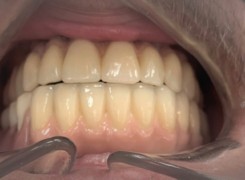

Pan Ryszard trafił do Naszego Gabinetu z jasno sprecyzowanym oczekiwaniem. Miał 84 lata i chciał odzyskać możliwość swobodnego spożywania posiłków oraz poprawienia sobie komfortu życia a także prosił aby przywrócić mu piękny uśmiech jakim cieszył się przed laty. Już na początku pierwszej rozmowy zastrzegł, że interesuje go wyłączenie rozwiązanie uzupełnieniem protetycznym stałym. Nie miał zamiaru użytkować żadnych protez ruchomych. Mając na uwadze powyższe wykonaliśmy Panu Ryszardowi zdjęcie pantomograficzne oraz badanie tomograficzne szczęki i żuchwy na postawie których zapanowywaliśmy Pacjentowi optymalne rozwiązanie – stałe uzupełnienie protetyczne w postaci 28 koron cyrkonowych zamontowanych do dwóch belek cyrkonowych które będą przymocowane do 16 implantów w konfiguracji 8 wszczepów w szczęcie 8 w żuchwie. Po omówieniu powyższego planu przystąpiliśmy do Wspólnej pracy której efekty w poszczególnych etapach prezentujemy poniżej.